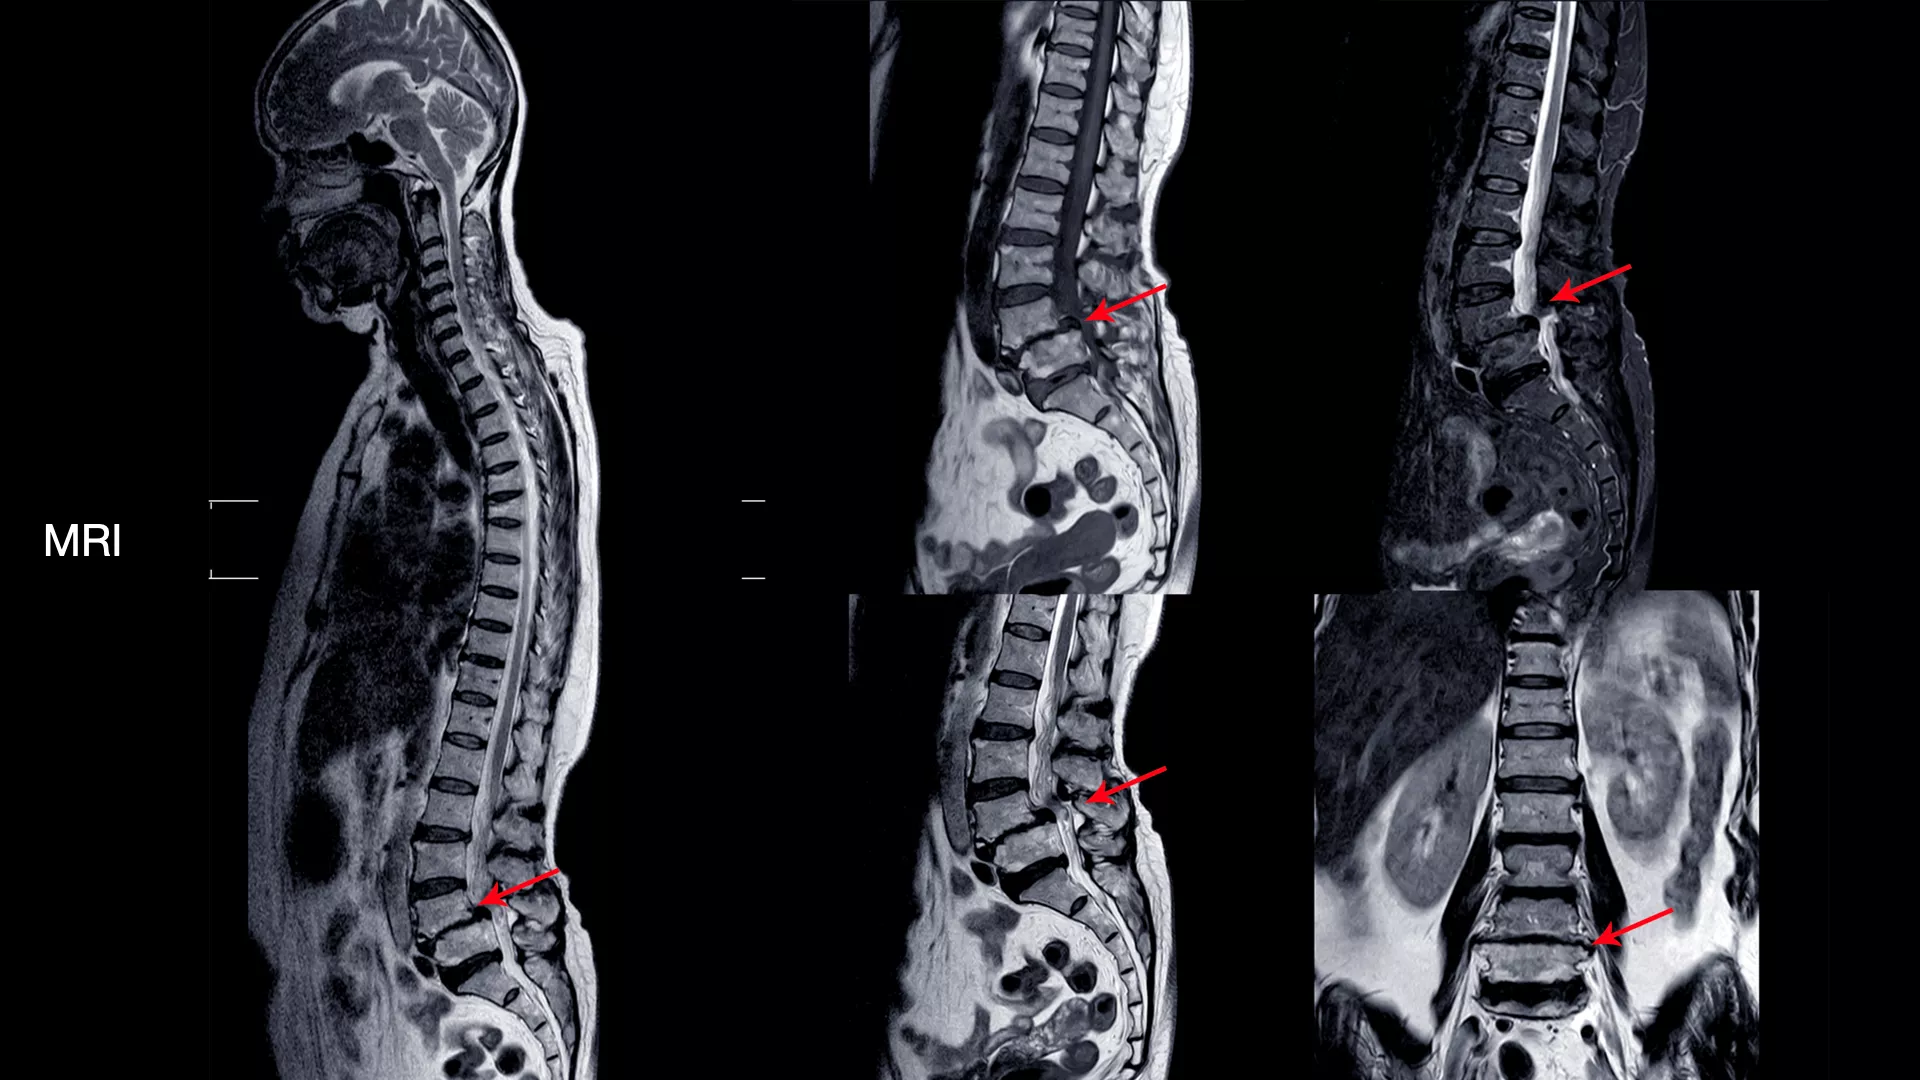

ดังนั้นการตรวจด้วย X-ray ทั้ง 4 ท่านี้จะช่วยให้แพทย์สามารถประเมินโครงสร้างของกระดูกสันหลังได้อย่างละเอียด และเป็นข้อมูลสำคัญในการพิจารณาแนวทางการรักษาที่เหมาะสมสำหรับผู้ป่วยแต่ละราย นอกจากนี้ การตรวจด้วย MRI (Magnetic Resonance Imaging) หรือ การสร้างภาพอวัยวะภายในร่างกายด้วยคลื่นแม่เหล็กไฟฟ้าและคลื่นวิทยุ โดยไม่ต้องใช้รังสีเอกซเรย์ที่เป็นอันตราย ก็มีความสำคัญอย่างยิ่งในการวินิจฉัยโรคกระดูกสันหลัง

เครื่อง MRI จะส่งคลื่นแม่เหล็กไฟฟ้าและคลื่นวิทยุเข้าไปในร่างกาย คลื่นเหล่านี้จะไปกระตุ้นโปรตอน (อนุภาคเล็กๆ ในอะตอม) ในร่างกายให้ปล่อยสัญญาณออกมา จากนั้นคอมพิวเตอร์จะแปลงสัญญาณที่ได้รับเป็นภาพ 3 มิติที่มีความละเอียดสูง ทำให้แพทย์สามารถเห็นรายละเอียดของเนื้อเยื่ออ่อนต่างๆ ได้อย่างชัดเจน

ดังนั้น การตรวจด้วย MRI จึงเข้ามาเติมเต็มในจุดนี้ โดยจะะให้ภาพที่มีความละเอียดสูงและสามารถเห็นรายละเอียดของเนื้อเยื่ออ่อนและลักษณะของรอยโรคได้อย่างชัดเจน ทำให้แพทย์สามารถ

- ระบุตำแหน่งและขนาดของรอยโรคได้อย่างแม่นยำ เช่น หมอนรองกระดูกปลิ้น หรือ หมอนรองกระดูกทับเส้นประสาท

- ประเมินความเสียหายของเส้นประสาท เห็นถึงระดับการกดทับของเส้นประสาทและไขสันหลัง